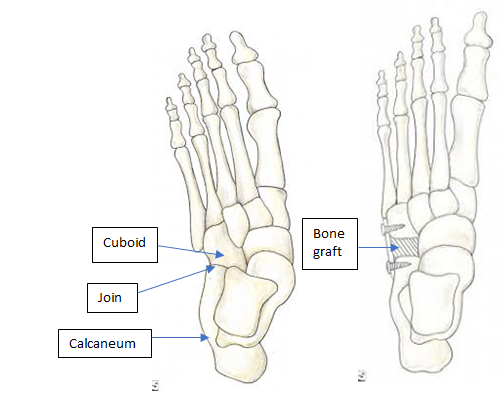

Calcaneocuboid distraction arthrodesis

In adults, lengthening the lateral border of the foot remains very effective in correcting a flat foot. However, the traditional Evans procedure is not always well tolerated with arthritis sometimes developing in the adjacent calcaneocuboid joint. This approach lengthens the lateral border of the foot by fusing the calcaneocuboid joint using a bone graft, preventing arthritis from occurring in this joint.

The downside is a stiffer foot and some patients still complain of pain affecting the lateral border of the foot. The fusion site can also be painful if the bones do not unite with the risk being around 2-4%.

The heel bone is cut and a bone graft taken and reinserted to lengthen the lateral border of the foot, increasing the arch height and stabilising the foot. It does not fuse any joints and the major movements of the foot are preserved, although the direction of movement is changed to prevent excessive rolling in of the foot.